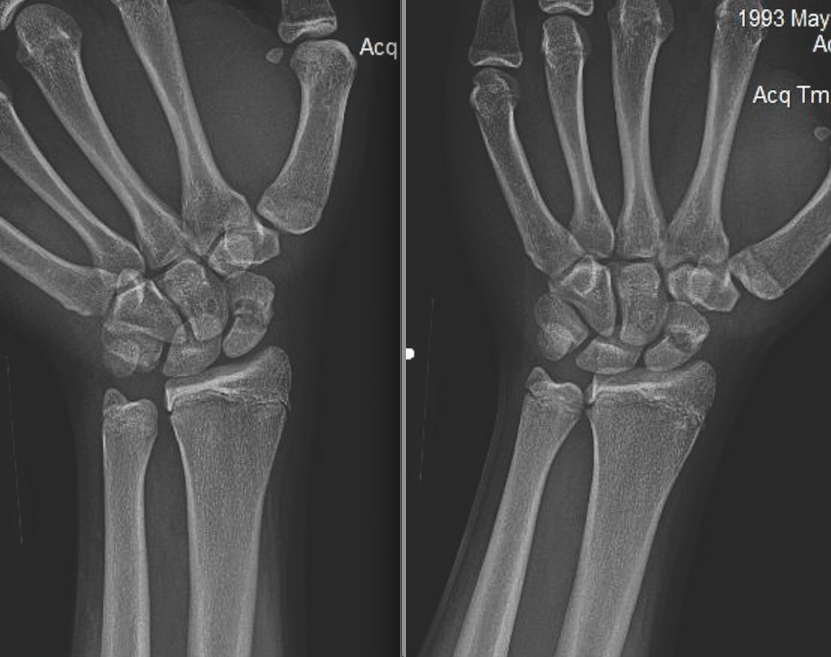

Roli Agrawal, MD

A 15-year-old previously healthy boy presented to the emergency department with a left wrist injury that had occurred 2 to 3 months ago.